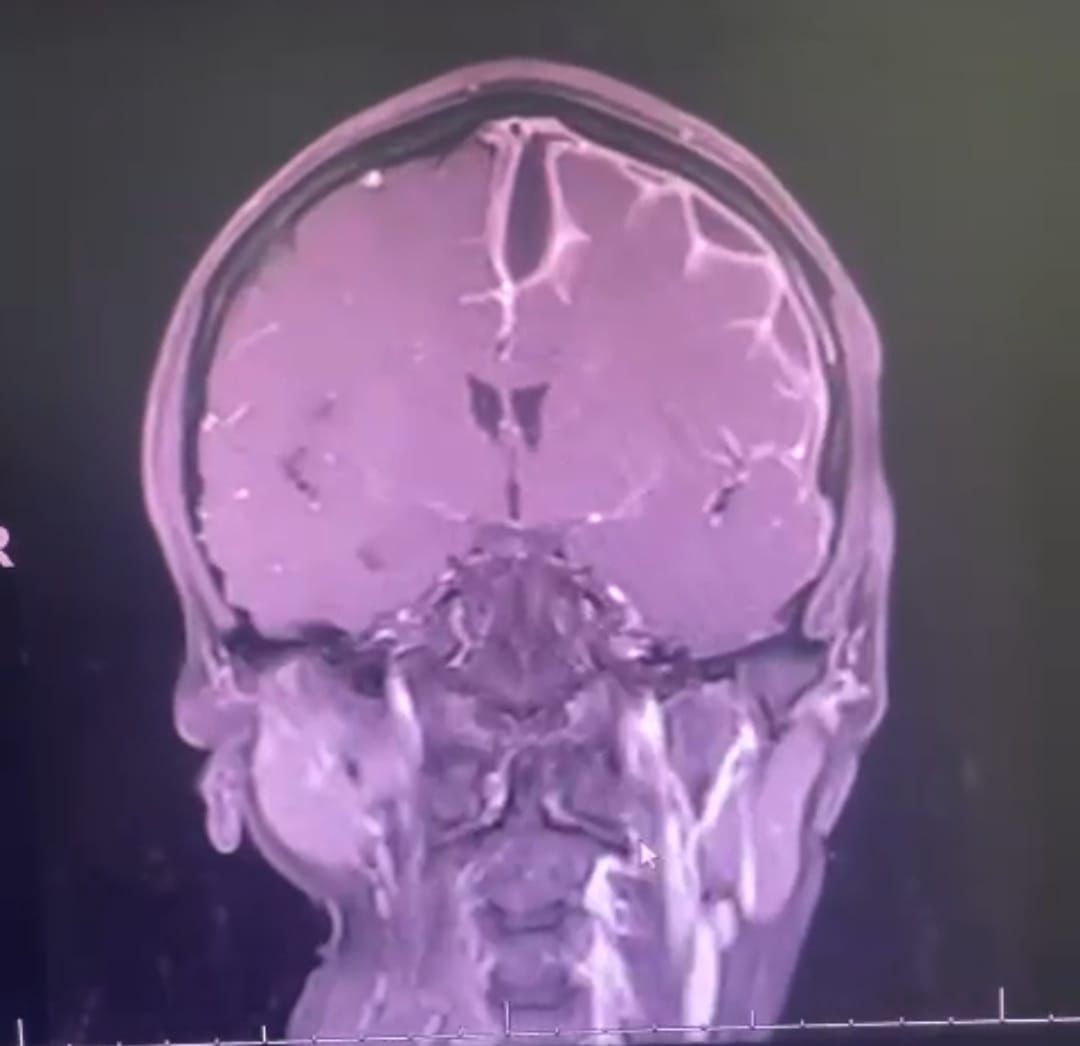

وأوضح تجمع الأحساء الصحي أن المريضة أُدخلت مستشفى الملك فهدبالهفوف عن طريق قسم الطوارئ؛ وهي تعاني من عدم قدرتها علىتحريك الأطراف اليمني وعدم القدرة على المشي، وعلى الفور تم إجراءالفحوصات السريرية اللازمة وعمل الاشعة والتي بينت وجود التهابشديد في الدماغ مع تجمع بؤرات صديدية تحت الام الجافية، وتقررإجراء عملية جراحية لرفع الجمجمة وسحب التجمعات الصديدية المتعددةفوق قشرة الدماغ وتحت الام الجافية و تقليل ضغط الدماغ .